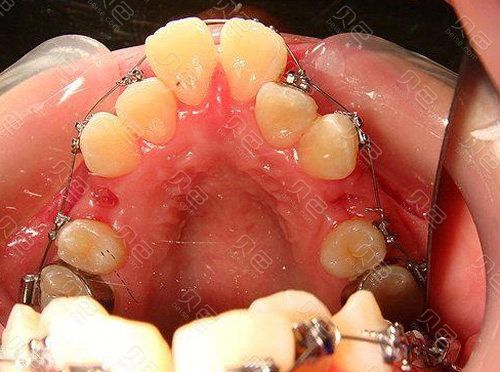

(图片来源网络,侵删) - 牙弓形态与对称性:

- 弓丝尺寸与材质:

T形曲通常在较粗的方丝(如0.016x0.022英寸或0.017x0.025英寸不锈钢丝或β钛丝)上弯制,弓丝的刚度和弹性决定了T形曲产生的力量大小和持续时间。